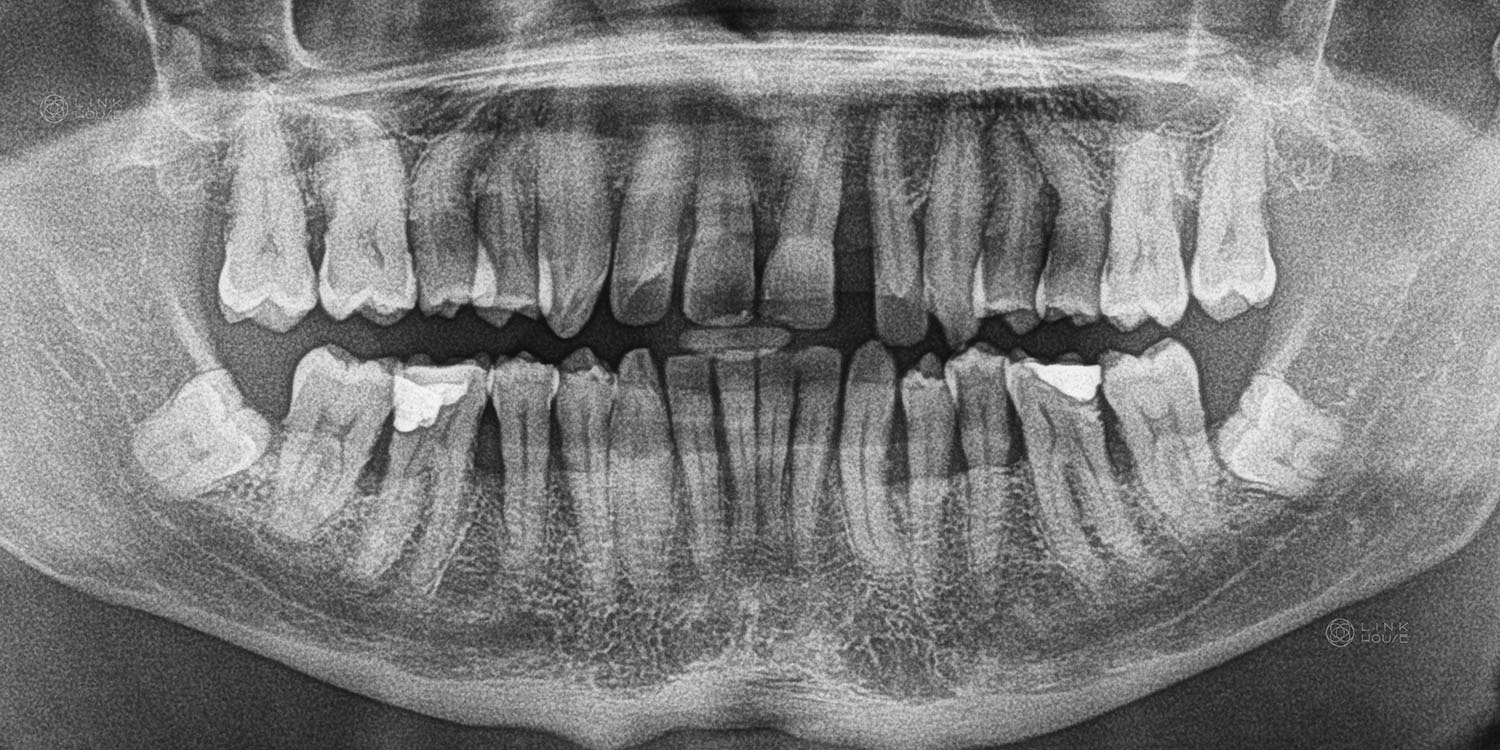

The wisdom tooth (or third molar) is usually the last tooth to erupt into the mouth, usually after 16 years of age. Frequently, there is not enough room to accommodate wisdom teeth, so they do not come into the mouth normally. When this happens, the wisdom teeth are said to be “impacted”. Wisdom teeth are usually either impacted forward into the tooth in front or backward into the jawbone.

An impacted tooth can cause several problems. Most commonly, these include repeated attacks of infection in the gum surrounding the tooth, which leads to pain, swelling and bone loss. Food packing can also cause decay in the wisdom tooth or the tooth in front.